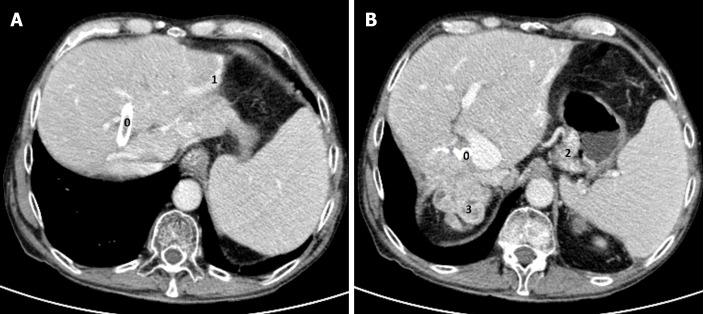

A 70-year-old man presented to the emergency department with diminished consciousness and disorientation, and was diagnosed with hepatic encephalopathy. The patient was diagnosed in 1993 with a metastatic small bowel NET, for which he twice underwent hepatic surgery, with metastatic resection in 1993 and a right hepatectomy in 2002 to remove two hepatic metastases. In 2003, the patient started first-line chemotherapy and in 2004 started the first of three consecutive biological treatments, followed by radio-molecular therapy, achieving stable disease for 14 years. Disease progression was identified and he underwent an endoscopic retrograde cholangiopancreatography. However, in 2019 advanced liver disease was identified. We diagnosed the development of acquired hepatocerebral degeneration, an unusual long-term side effect after multiple hepatic procedures.

一名70岁男性因意识减退和定向障碍就诊于急诊科,被诊断为肝性脑病。该患者于1993年被诊断为转移性小肠NET,为此他接受了两次肝脏手术,1993年进行了转移性切除术,2002年进行了右肝切除术以切除两处肝转移灶。2003年,患者开始一线化疗,2004年开始连续三次生物治疗中的第一次,随后进行放射分子治疗,病情稳定了14年。发现疾病进展后,他接受了内镜逆行胰胆管造影术。然而,2019年发现了晚期肝病。我们诊断为获得性肝脑变性的发生,这是多次肝脏手术后一种不常见的长期副作用。